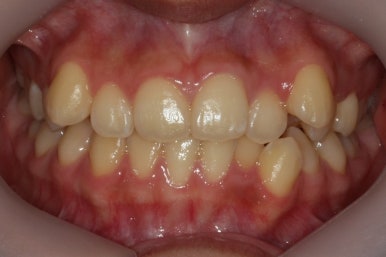

이제 치료가 끝났습니다.

매우 치아가 가지런해졌고, 당연히 덧니는 해소가 되었으며 맞물림도 굉장히 좋아졌습니다.

치아가 매우 가지런해졌고, 덧니도 개선이 되었습니다.

맞물림도 굉장히 좋아졌네요.